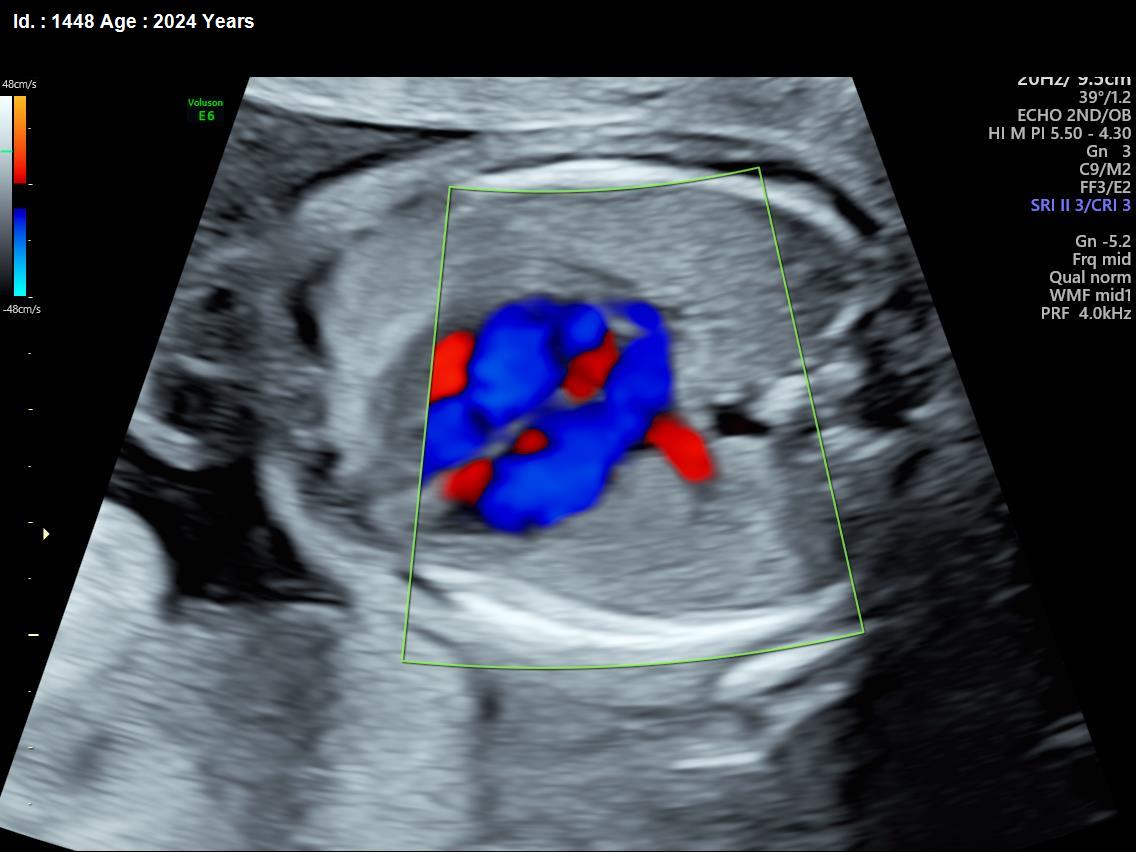

It is a test similar to ultrasound. It allows the doctor to see structure and function of the baby’s heart in detail. It also enables the doctor to see blood flow through fetal heart and cardiac rhythm. The scan is done by a radiologist or a fetal medicine specialist.

A fetal echocardiogram focuses specifically on the fetal heart, providing a detailed examination of its structure and function. In contrast, a standard ultrasound assesses overall fetal development and growth.